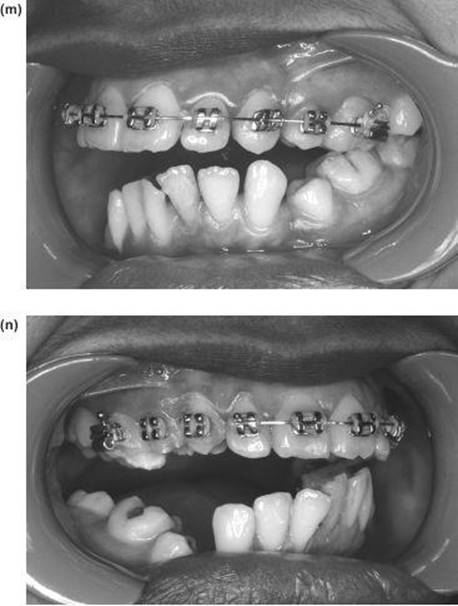

7. The nasal septum and pterygoid plates are separated intraorally, as in the Le Fort I operation.